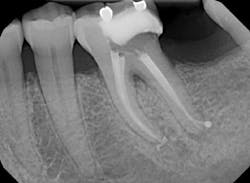

Next, the canals were shaped using GTX Files. Initially, a 40-.06 was taken to resistance. At this time, a crown down method was used going from 30-.06 to 20-.06. Final shape was determined to be a 30-.06 for all canals. These were confirmed using a shape verifier (provided with Guttacore obturators) and an apex locator.

Canals were irrigated with full-strength sodium hypochloride and Q-mix and agitated with an EndoActivator for one minute in each canal. Next, the canals were dried and sealer was applied with a paper point in the coronal half of the canal.

Obturation was completed by slowly placing the Guttacore obturators to length and removing the handles with a sharp spoon excavator. It can be noted that Obturation looks complete and an apical dilacerations was picked up on the distal canal.